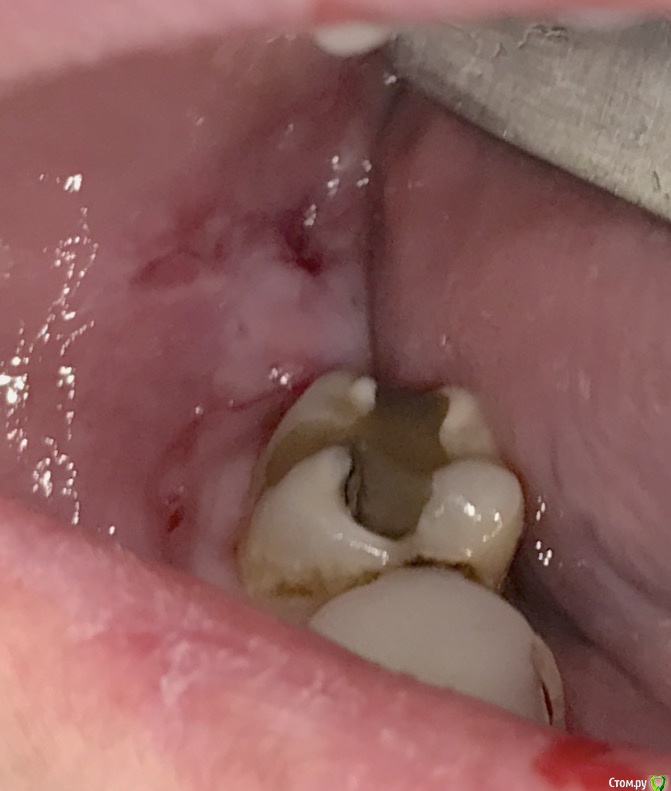

колесников Опубликовано 25 марта, 2017 Автор Поделиться Опубликовано 25 марта, 2017 Повторение-мать учения 1 Ссылка на комментарий

Irouil Опубликовано 25 марта, 2017 Поделиться Опубликовано 25 марта, 2017 Это язычный? Ссылка на комментарий

колесников Опубликовано 25 марта, 2017 Автор Поделиться Опубликовано 25 марта, 2017 Он Ссылка на комментарий